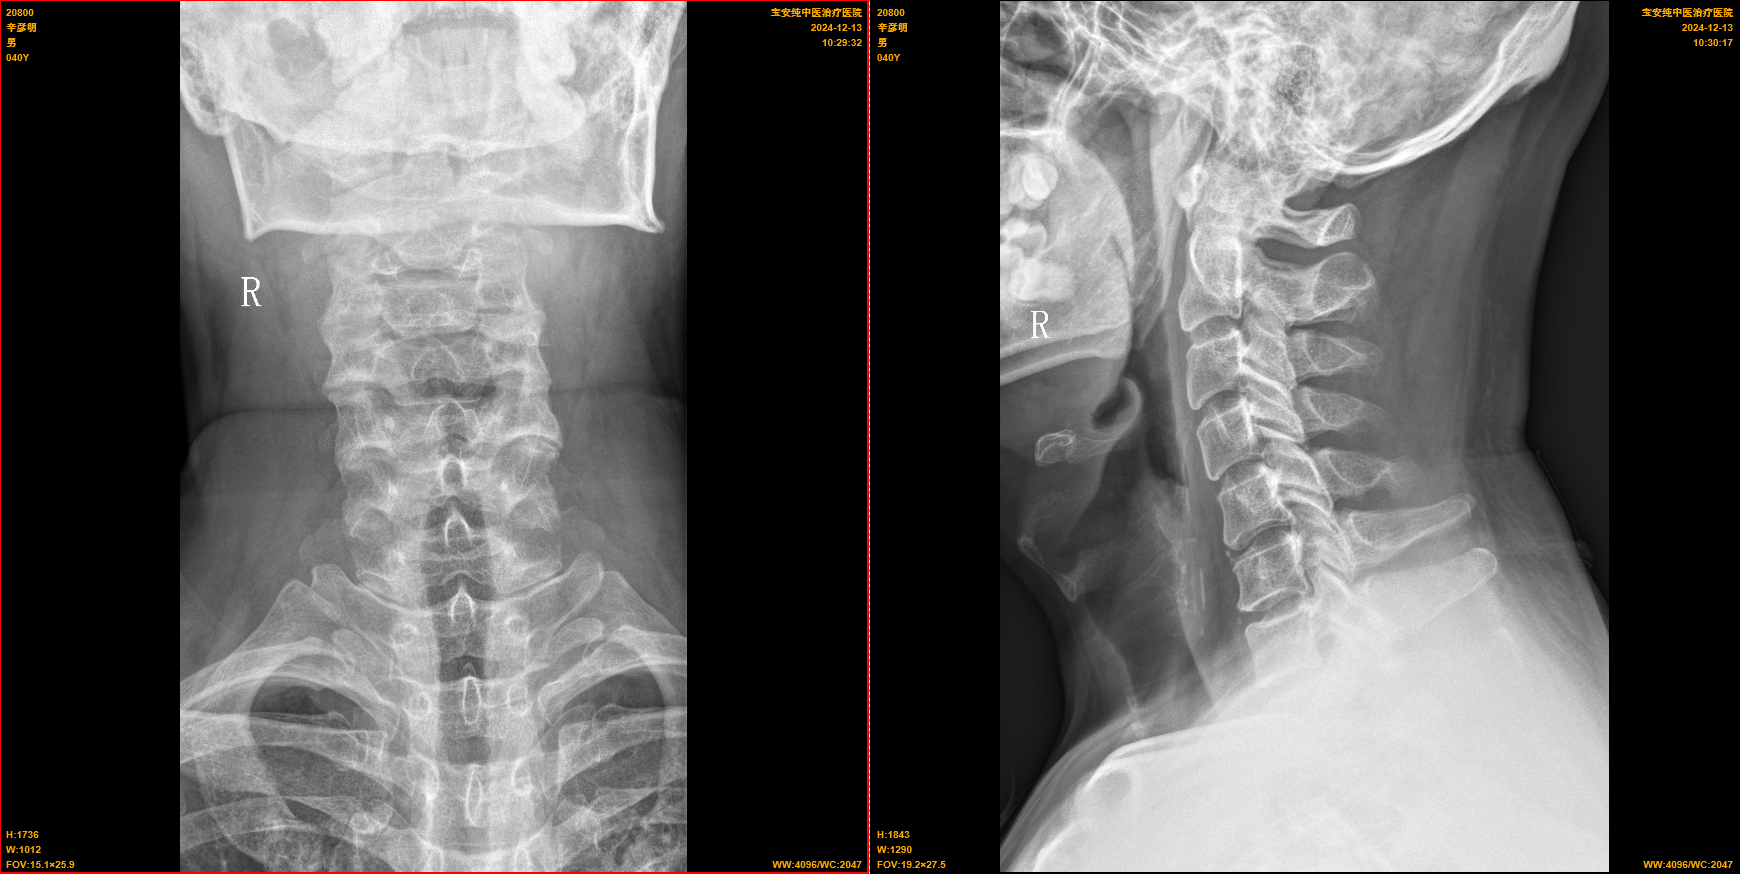

【影像】20241102龙岗骨科医院CT报颈椎曲度变直,C3-6间盘突出(中央型),C6-7间盘突出(右旁中央型),继发椎管狭窄,右侧神经根受压。颈椎X线片报颈椎退行性变。阅片见颈椎向右侧倾,C5-6角折,左侧C3-5椎间孔变小,上位椎体下关节突向后下移位。

【讨论】患者左侧肩胛间区疼痛,仰头加重;左侧椎间孔挤压试验(+),引发左侧肩胛间区疼痛;左侧C4-5椎间孔变小,上位椎体下关节突向后下移位;诊断为神经根型颈椎病。肩胛间区为斜方肌、菱形肌、竖脊肌、上后锯肌所在,查体未见明显肌紧张及条索,基本排除局部肌肉损伤。后仰时左侧肩胛间区疼痛,考虑颈椎刺激肩胛背神经所致。椎间孔挤压试验(+)、X线片见C4-5椎间孔狭窄证实推断正确。

颈椎CT报C3-7间盘突出、C6-7水平椎管狭窄伴右侧神经根受压,因其未引发相应临床症状,故不予诊断。X线片见C5-6角折,颈椎后伸时C5以下椎体不能正常后伸运动,C3-5关节突关节反复超范围后伸而错位,C3-4错位尚未挤压相应神经,C4-5错位刺激C5神经(肩胛背神经)引发肩胛间区及上臂上段疼痛。故治疗时复位C4-5关节突关节治其标,纠正C5-6角折加大C5以下颈椎后伸范围治其本,复位C3-4关节突关节未病先防。